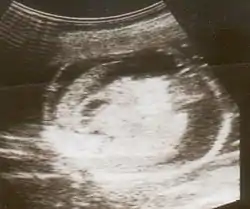

![]() تصوير بالموجات فوق الصوتية لجنين مصاب بالاستسقاء الجنيني تصوير بالموجات فوق الصوتية لجنين مصاب بالاستسقاء الجنيني | |

يتم الكشف عنه بواسطة جهاز التصوير فوق الصوتي ونشاهد فيه: